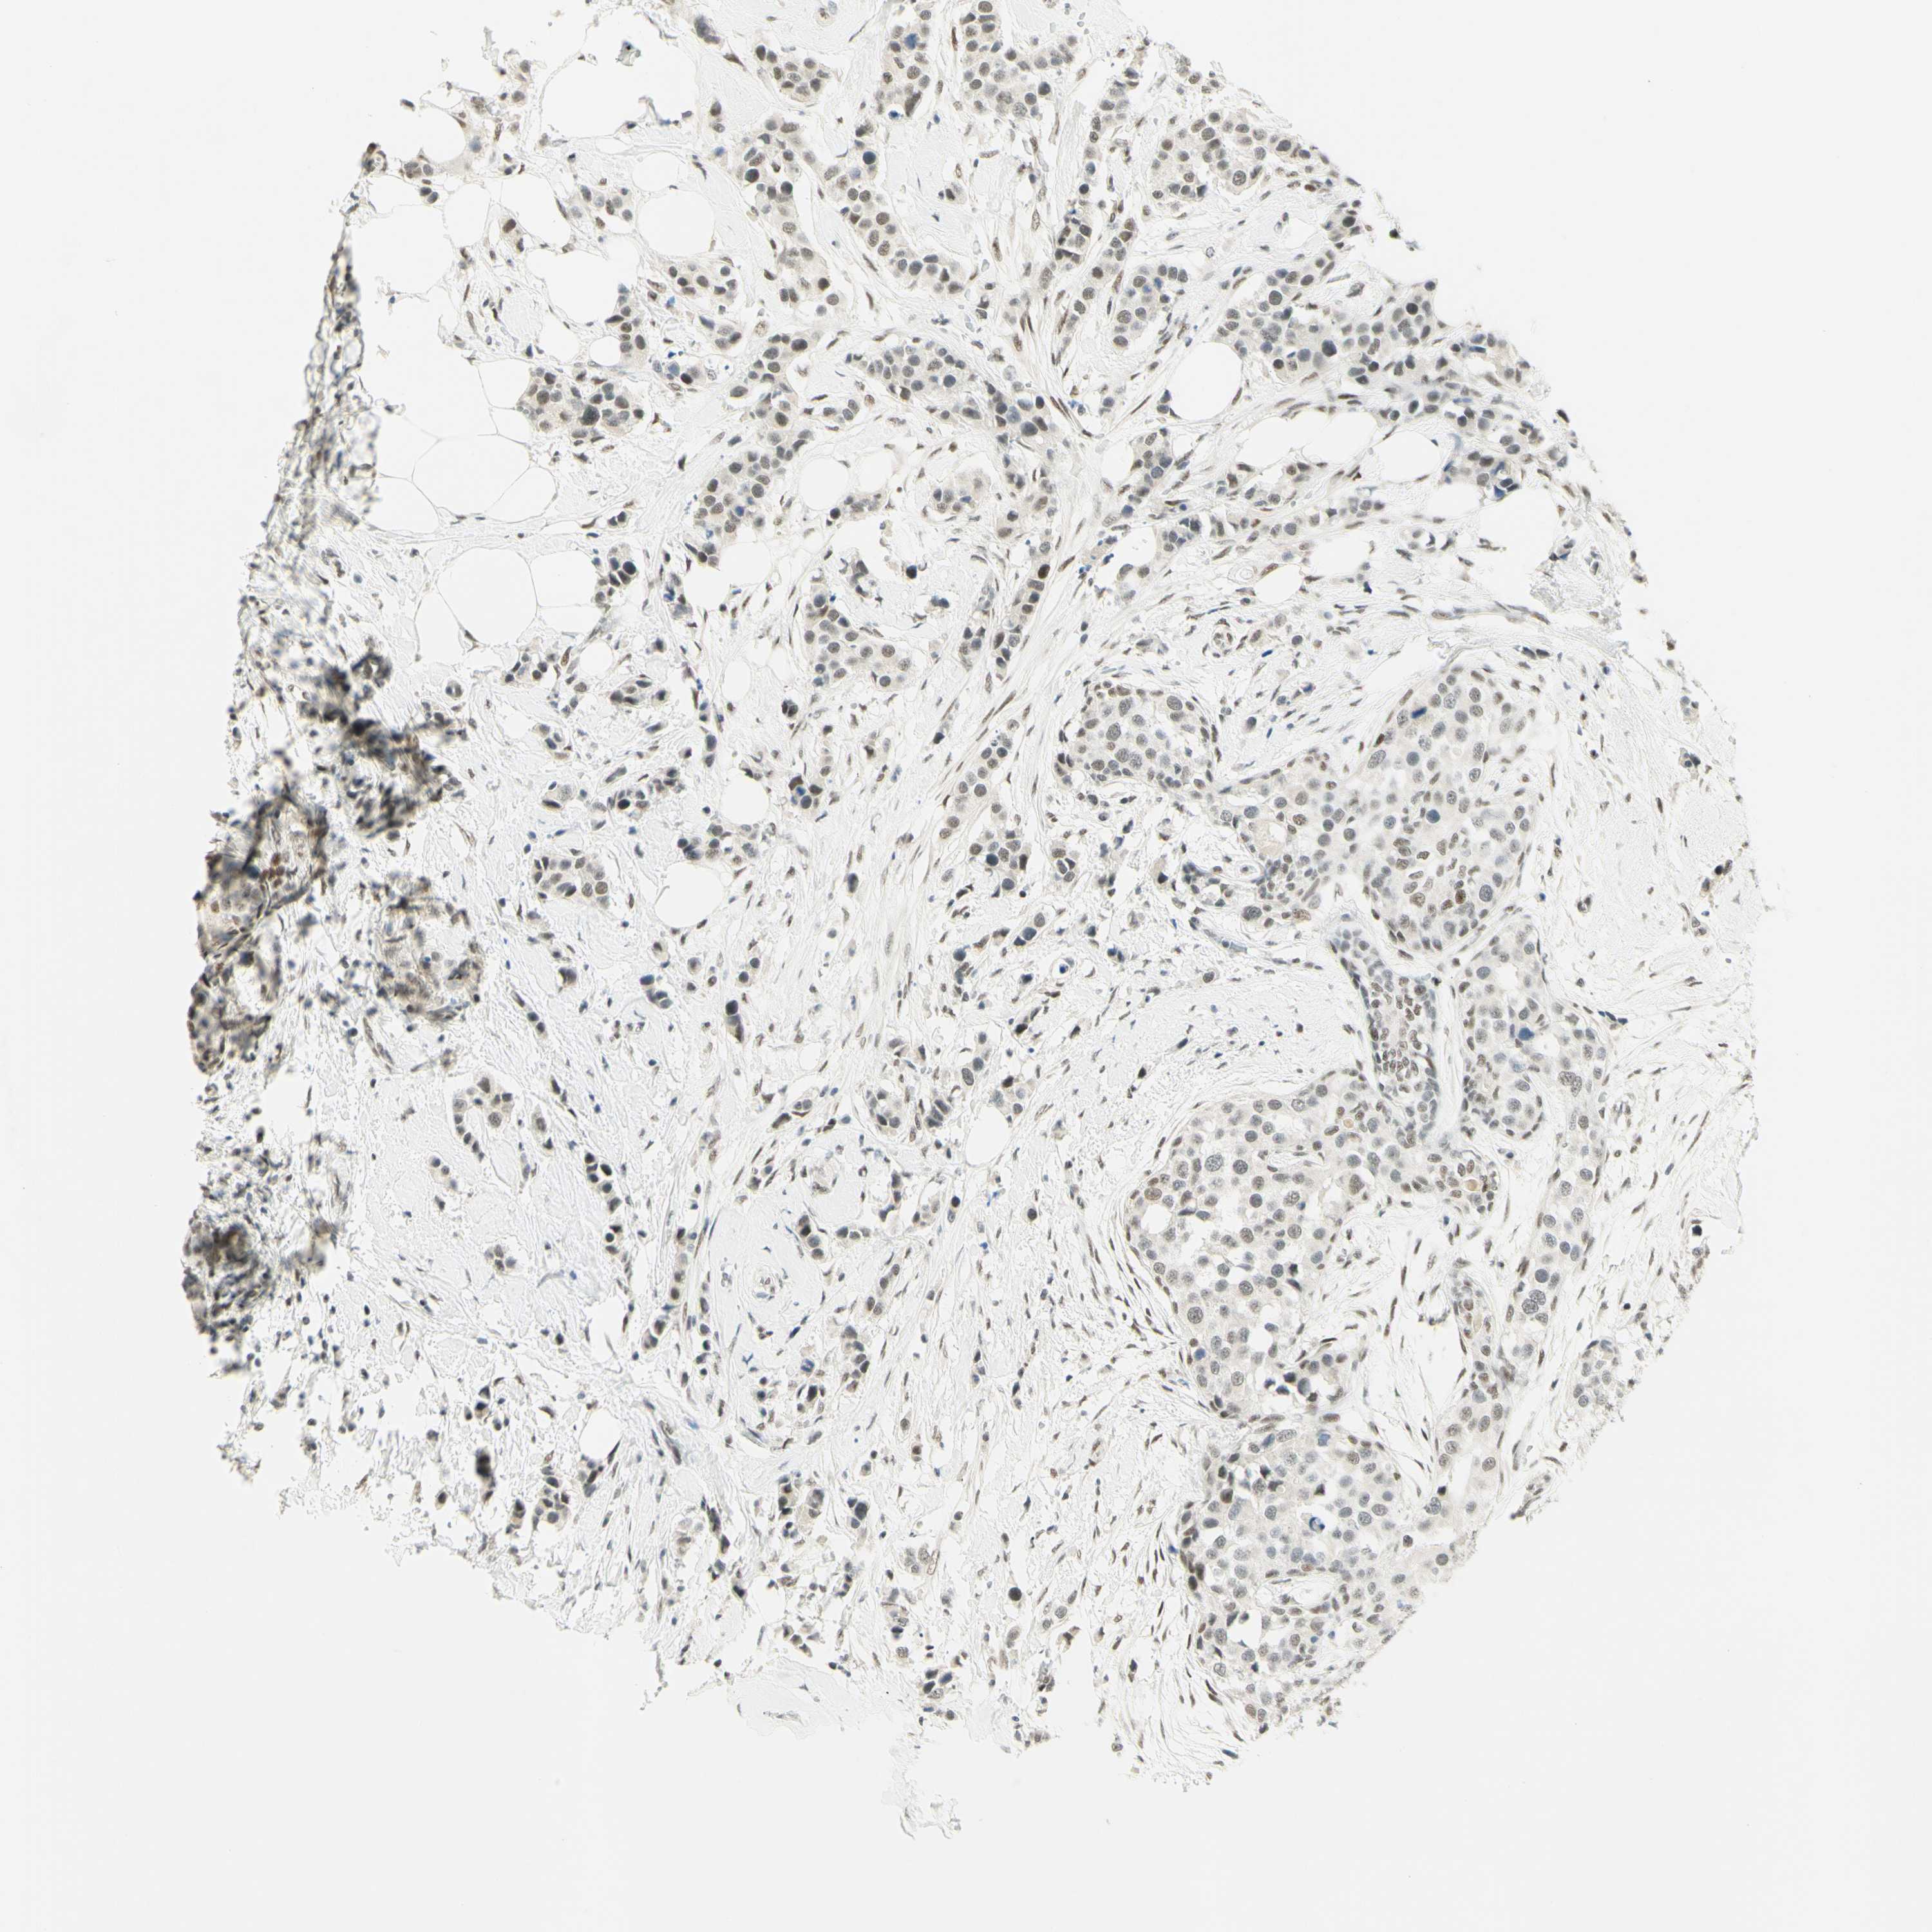

CANCER BREAST CANCER Show tissue menu

BRCA TCGA BRCA VALIDATION PROTEIN EXPRESSION

ANTIBODIES

AND

VALIDATION